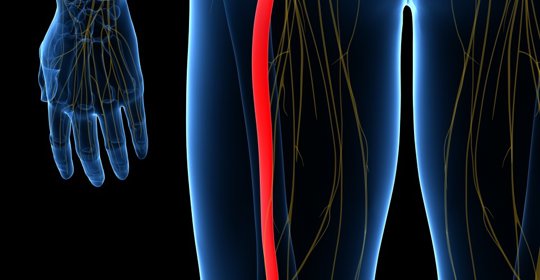

股神經痛:飲食注意與醫護幹預

股神經痛:治療與管理

股神經傷害:建議就診科室

股神經痛:拉筋與就醫

股神經痛:飲食與用藥注意